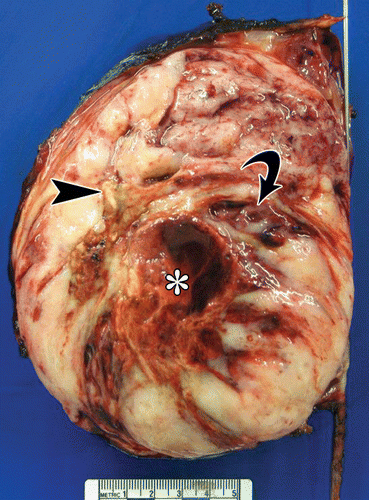

Picture of nephroblstomatosis + Wilms

Wilms tumor,

Staged 1,2,3,4,5. Stage 5 is bilateral and requires independent classification